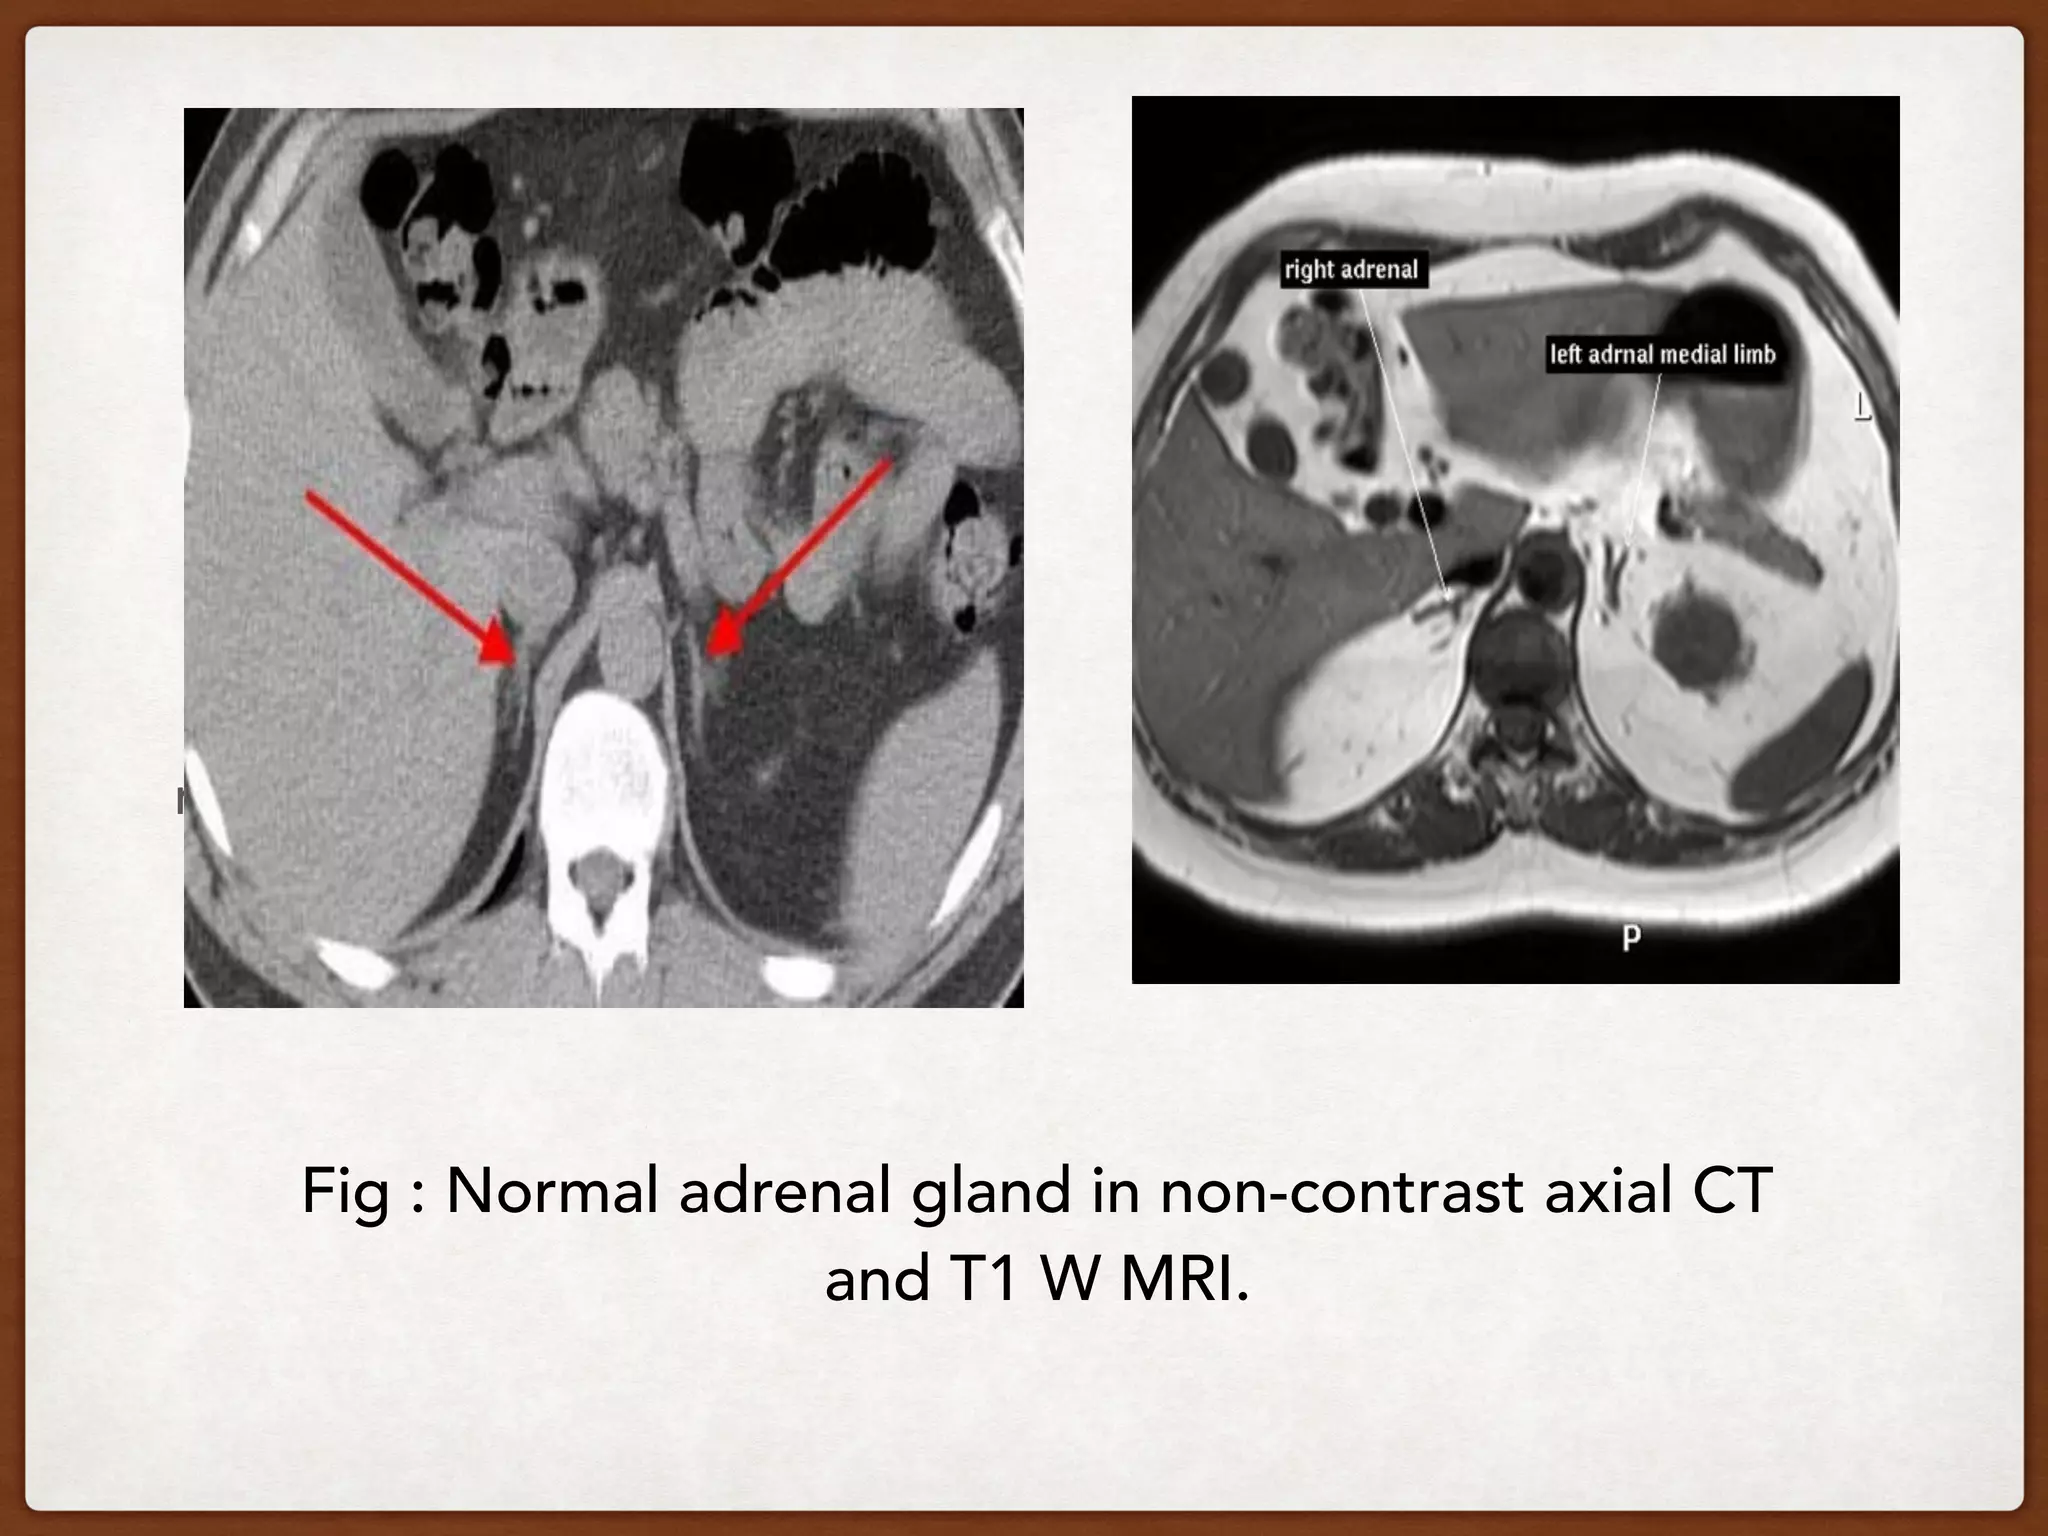

Fig : Normal adrenal gland in non-contrast axial CT

and T1 W MRI.

nnee Fig : Normaladrenal gland in non-contrast axial CT and T1 W MRI.